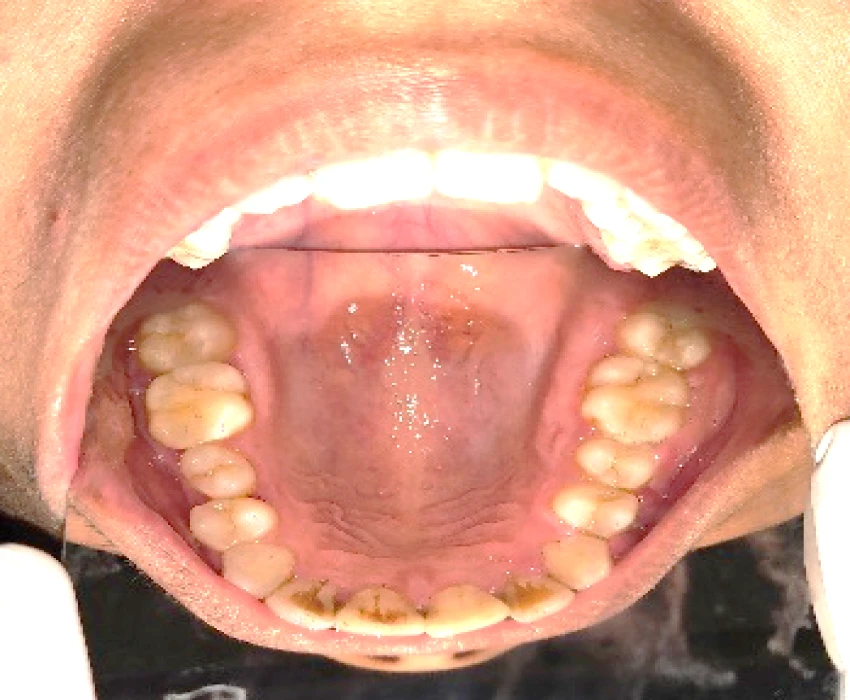

A 20 years old female patient reported to the department of oral medicine and radiology with a chief complaint of pain and swelling in the upper left back region of the jaw since 1 year. Provisional diagnosis was made as Gingival Fibromatosis.